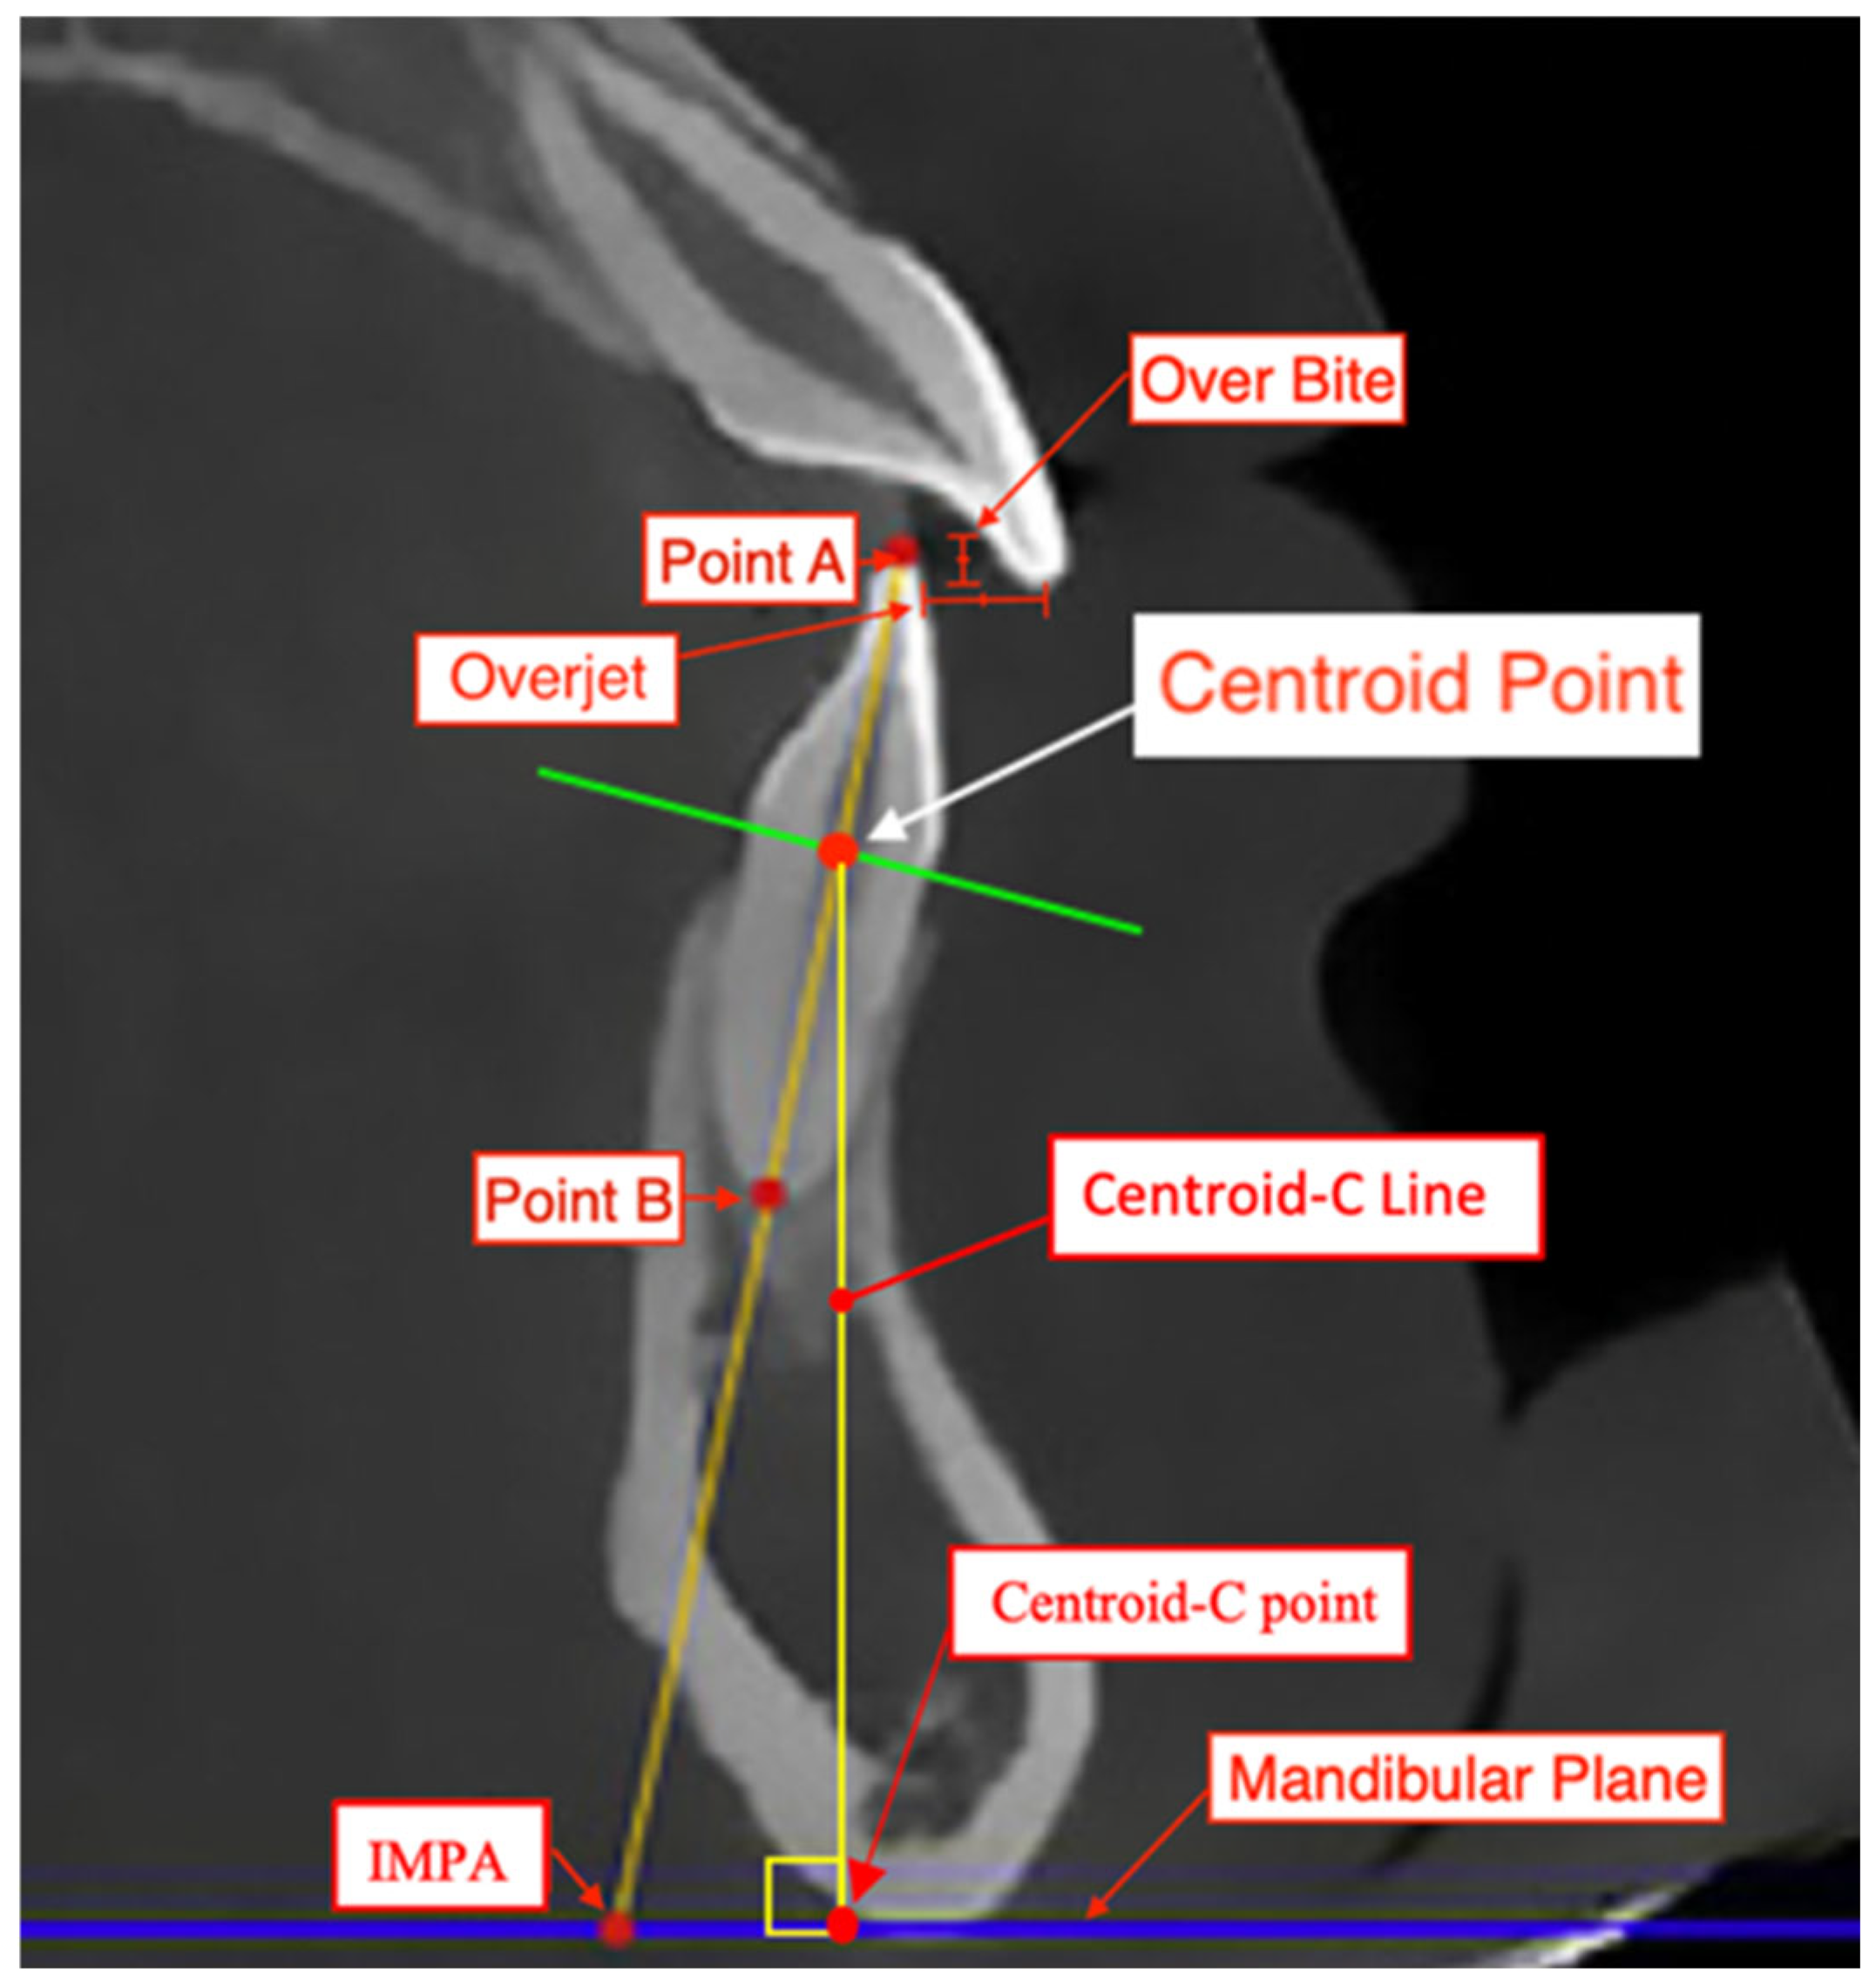

All measurements were conducted by one examiner (CB) who was pre-calibrated and trained in cephalometric assessment. The same examiner (CB) remeasured records from 10 randomly selected patients to assess intra-observer reliability. A second calibrated examiner (AG) measured records from 10 randomly selected patients to assess inter-observer reliability. The methodology for assessment will be similar to that in the study by Al-Balaa et al. [7] in determining the total intrusive movement of mandibular central incisors. First, the landmarks of a centroid point were established at the intersection of a horizontal line constructed from the cementoenamel junction (CEJ) of the facial and lingual surfaces of the lower central incisor and the vertical axis of the lower central incisor on a lateral cephalogram (Figure 1). The IMPA, L1 to APo, and L1 to NB were established using Dolphin software version 11.95 and the Steiner [12], Tweed [13], and Ricketts [14] cephalometric analyses (Figure 2). These measurements were made on pre-treatment (T1) and on post-treatment (T2) lateral cephalograms. A tooth’s total intrusion was determined by the decrease in distance from the centroid point to the mandibular plane (Centroid-C Line) in T1 to T2. IMPA, L1 to APo, and L1 to NB were also recorded for T1 and T2. The total intrusion of each tooth was then contrasted with the total intrusive movement predicted in the ClinCheck software [15,16,17,18]. The change in inclination of IMPA, L1 to APo, and L1 to NB from T1 to T2 were also contrasted with the predicted degree of change in the ClinCheck software.

Figure 1. Lower incisor intrusion measurement landmarks. Point A (incisal tip): most coronal point of lower mandibular anterior tooth from sagittal view at buccolingual and mesiodistal midpoint. Point B (root apex): most apical point of lower mandibular anterior tooth from sagittal view at buccolingual and mesiodistal midpoint. Centroid-C Point: intersecting perpendicular point of Centroid-C line with mandibular plane. Centroid point: central point of lower central incisor identified from midpoint formed from buccal and lingual CEJ. AB line: line segment created from A point to B point and total estimated length of tooth. Centroid-C line: line segment from tooth centroid to mandibular plane forming right angle at mandibular plane and estimated spatial vertical position. Overbite: overlapping of mandibular central incisor teeth by maxillary central incisor teeth. Overjet: extent of anterior–posterior of maxillary central incisor to mandibular central incisors.